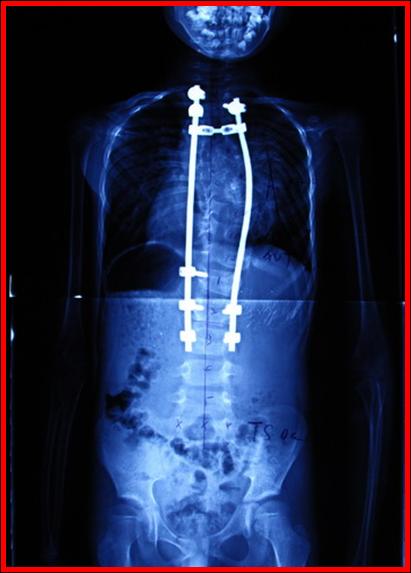

术后X线

截止2010年11月,北京协和医院骨科对124例明确诊断为先天性脊柱侧弯合并脊髓纵裂、且未出现神经症状或神经症状稳定期大于两年的患者行单纯矫形术。并对其中73例患者进行了2年以上随访,平均随访时间为5.3年,所有患者术后矫形均在50%以上,且无一例发生神经系统并发症。以上数据表明协和骨科所行单纯脊柱侧弯矫形手术安全、有效。